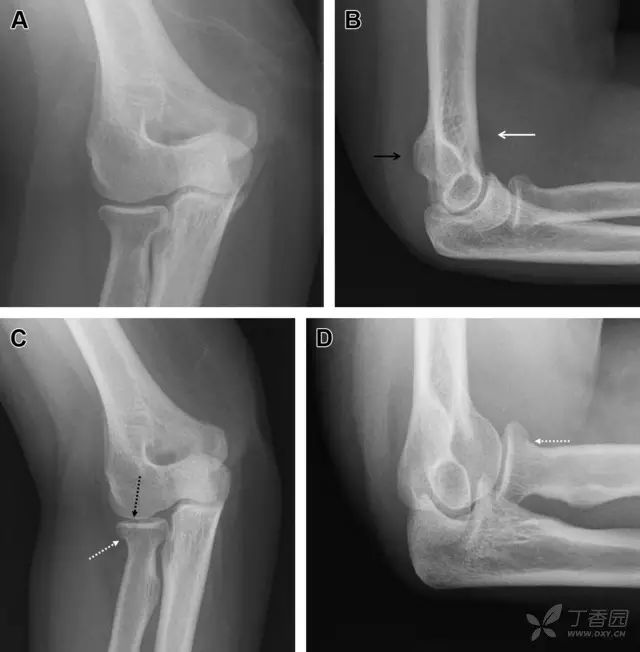

膝关节撕脱骨折和压缩骨折常伴发于韧带损伤,若想准确诊断,在了解这些骨折高发部位的同时,还需仔细认真地阅片,否则有些骨折就被漏诊了。

前交叉韧带撕脱骨折常发生在胫骨髁间嵴(图 1)。这种骨折在青少年中常见,但在成年人中也并不像大家想象的那么少见。

图 1 摩托车事故患者前交叉韧带撕脱性骨折

A 正位片示胫骨髁间嵴底部骨折(箭头),注意别把这个骨折碎片错认为关节内结构。B 侧位片示胫骨上方可见一细长型骨折碎片(椭圆)。C MRI 矢状位 T2 加权像示前交叉韧带附着于撕脱的骨折碎片上(箭头),注意周围存在骨髓水肿和积脂血征(空箭头)。

图 2 扭伤后的股骨外侧髁凹陷征

A 侧位片示股骨外侧髁凹陷。B MRI 矢状位 T2 加权像示股骨外侧髁及胫骨后外侧骨挫伤(空箭头)。胫骨近端随着后交叉韧带撕裂发生移位,露出外侧半月板的后角(弧形箭头)。

胫骨后外侧小片骨皮质的压缩性骨折,可能是旋转移位损伤的唯一证据(图 3)。这种骨折在常规膝关节平片很难发现,若怀疑存在骨折,行下肢内旋斜位片检查可诊断。

图 3 胫骨后外侧碎片骨折

A 正位片示胫骨后外侧处可见一压缩骨折的小碎片(方框)。这是胫骨撞击股骨外侧髁旋转移位时所致。B 另一位患者的 MRI 矢状位 T1 加权像示胫骨后外侧骨折碎片(箭头)。

Segond 骨折是发生在胫骨平台外侧的垂直撕脱性骨折(图 4)。这种骨折在前后位 X 线片上显示最佳。

屈曲位时膝关节受到内旋暴力作用,导致皮质骨撕脱性骨折,这种骨折常发生在运动员身上。常引起股骨内髁和胫骨平台后内侧骨挫伤,75%~100% 的患者伴前交叉韧带断裂,33% 的患者伴外侧半月板损伤。

图 4 一位足球运动员的 Segond 骨折

A 正位片示关节线下方胫骨外侧皮质撕脱(箭头)。B MRI 冠状位 T1 加权像示附着于髂胫带的骨折碎片(空箭头)。